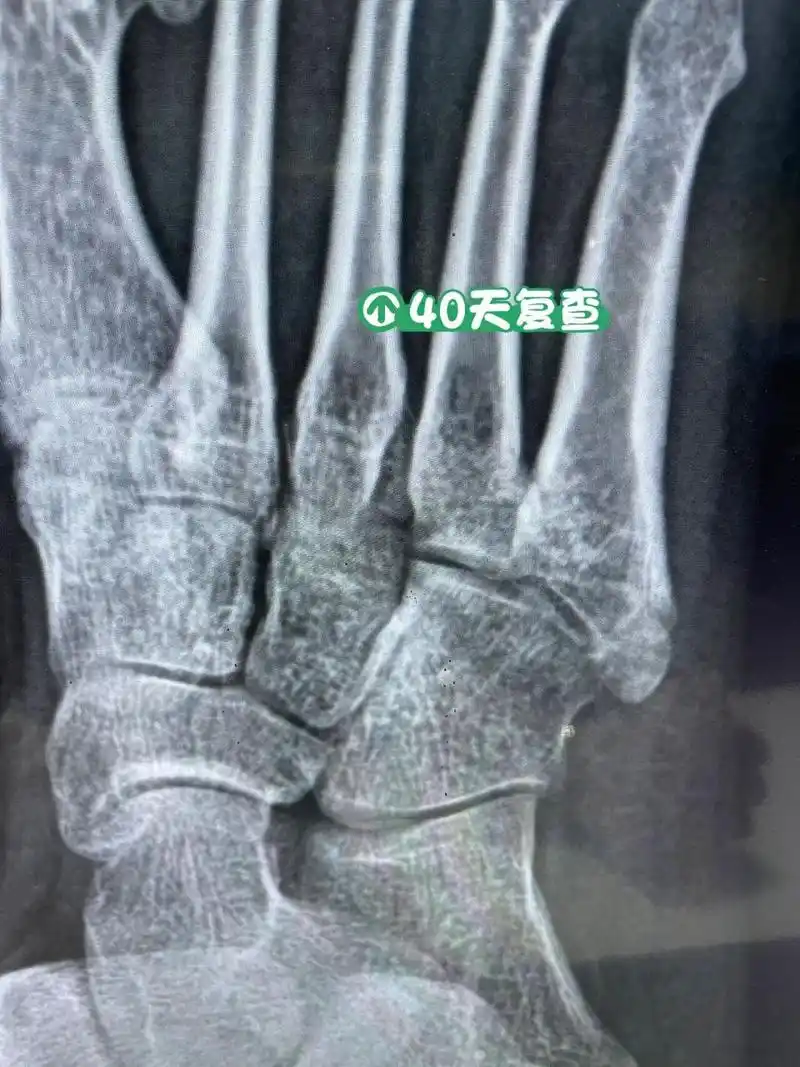

第五跖骨基底骨折40天复查 骨折40天了,还有一点缝,脱拐走路一星期